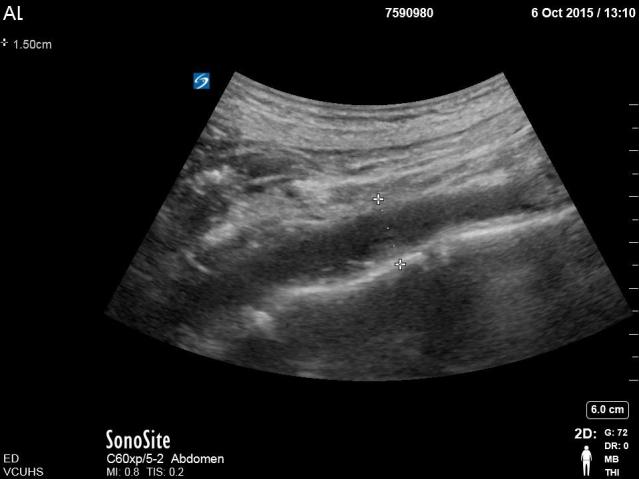

B. Measurement of distal aorta (just prox to bifurcation) from outer to outer wall + clip showing bifurcation